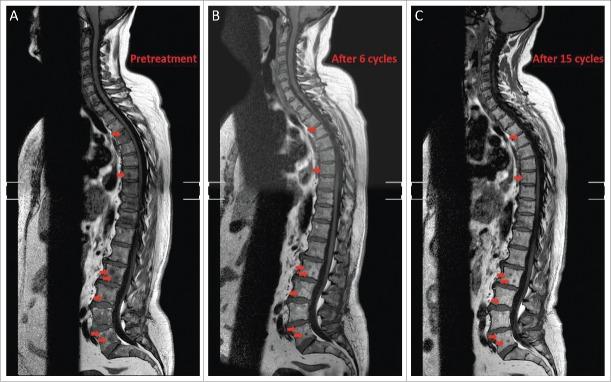

The occurrence of skin metastases is a common event in patients affected by advanced breast cancer, usually associated with systemic disease progression. Here we describe 2 cases of diffuse cutaneous metastases from HER2-overexpressing breast cancer occurring despite a dramatic response in liver and bone, respectively, during treatment with anti-HER2 antibodies Trastuzumab and Pertuzumab. We discuss the reasons for this discrepancy and suggest a possible implication of impaired immune response in the skin. Future research should provide strategies to overcome the induction of immune privilege in the skin in order to avoid discontinuation of effective treatments.

皮肤转移的发生在晚期乳腺癌患者中是常见事件,通常与全身疾病进展相关。在此,我们描述2例HER2过表达乳腺癌的弥漫性皮肤转移病例,尽管在使用抗HER2抗体曲妥珠单抗和帕妥珠单抗治疗期间,肝脏和骨骼分别出现了显著反应,但仍发生了皮肤转移。我们讨论了这种差异的原因,并提出皮肤免疫反应受损可能起到了一定作用。未来的研究应提供策略,以克服皮肤中免疫特权的诱导,从而避免中断有效的治疗。